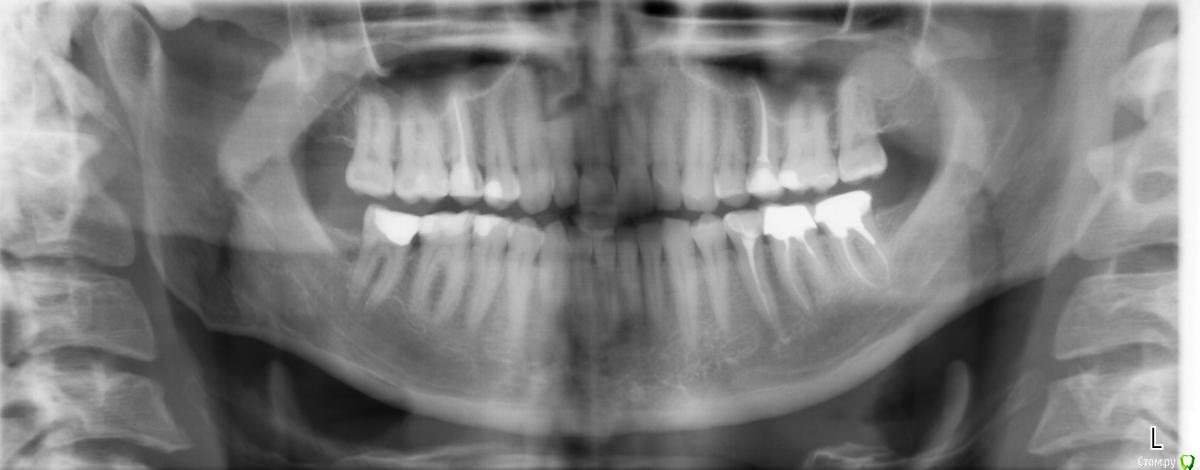

У меня частично оголились шейки клыков и одного близлежащего к каждому из них зуба. По виду напоминает клиновидный дефект.

Стоматолог-ортопед поставил мне диагноз пародонтит. При этом сказал, что оголение шеек указанных зубов произошло из-за неправильного прикуса (хотя когда сжимаю зубы - нагрузки на клыки не чувствую). Его план лечения включает в себя изменение прикуса, а именно, увеличение нагрузки на жевательные зубы путем установления на них коронок (по одной) и замены пломб.

Из предварительных обследований помимо снимка (приложение), делал слепок челюсти (т.е. когда вставляют в ротовую полость штуковину с синим подобием пластилина, который постепенно застывает).

post-45654-0-27679300-1448917650_thumb.jpg